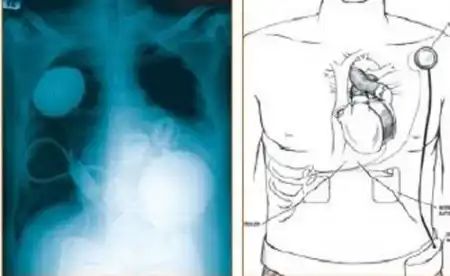

А это полностью искусственное сердце, которое является альтернативой пересадке донорского органа...

Оно достойно выполняет функции насоса, позволяя снабжать кровью всю кровеносную систему человека...